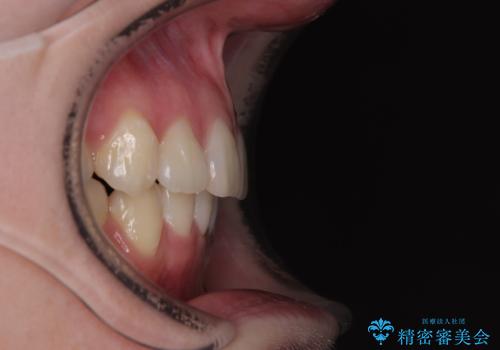

上下の八重歯とクロスバイト ワイヤー装置での抜歯矯正

上下ともに八重歯が顕著であり、前歯のクロスバイトがあったため、上下左右の第一小臼歯4本を抜歯し、ワイヤー装置での抜歯矯正を行うこととしました。